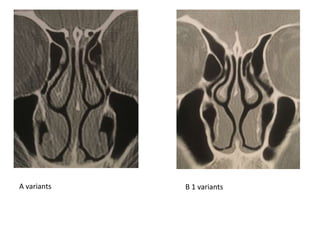

Anatomiskās variācijas:

• A Recessus frontalis drenējas uz vidējo deguna

eju

• B1; B2 - Recessus frontalis drenējas uz

infundibulum ethmoidale

• Svarīga arī priekšējo etmoidālo šunu

anatomija

A variants B 1 variants

B 2 variants Intersinus septal cell drenējas uz

kreiso pusi

Anatomiskās variācijas: • ARecessus frontalis drenējas uz vidējo deguna eju • B1; B2 - Recessus frontalis drenējas uz infundibulum ethmoidale • Svarīga arī priekšējo etmoidālo šunu anatomija

A variants B1 variants

B 2 variantsIntersinus septal cell drenējas uz kreiso pusi